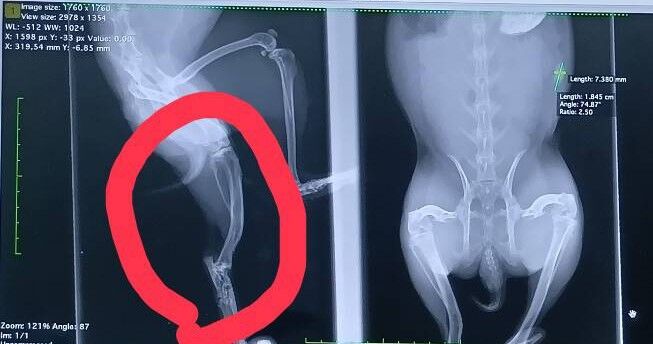

今回のレントゲンで右足に保護前に骨折した可能性がある湾曲が見つかりました。

将来的に左右で筋力差が出る可能性はありますが、現時点で生活に支障はないとのことでした。